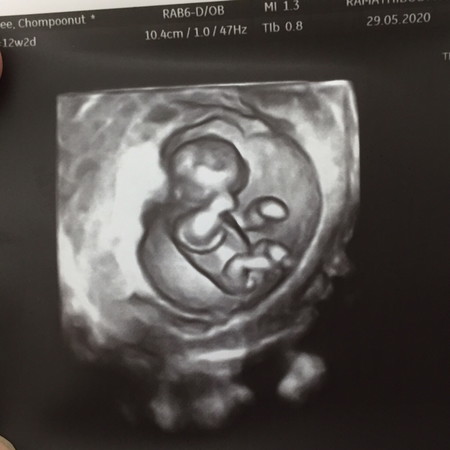

12w2d ทีมธันวาคมค่ะ โพสต์เมื่อ 29/05/20

เนื่องจากแม่อายุมาก วันนี้คุณหมอนัดตรวจ ก็อัลตราซาวด์ดูความสมบูรณ์ของน้องค่ะ ครั้งนี้ คุณหมอดูขนาดคออย่างคร่าวๆ ว่าหนามั้ยเพราะถ้าหนา มันคือ ลักษณะของ Down syndrome ซึ่งน้องไม่มีค่ะ ? แต่นัดครั้งหน้า แม่ต้องเจาะน้ำคร่ำ เพื่อดูผลแบบ 100% ค่ะ วันนี้คุณหมอดูเพศให้ด้วย บอก 80% เป็นผู้หญิงค่ะ ??

ตรวจคราวหน้าก็จะดูความสมบูรณ์ที่ละเอียดขึ้น เช่น นับนิ้วมือ นิ้วเท้าค่ะ ความหมาย ก็คือ ตรวจความสมบูรณ์ตามอายุครรภ์นั่นเองค่ะ 😊